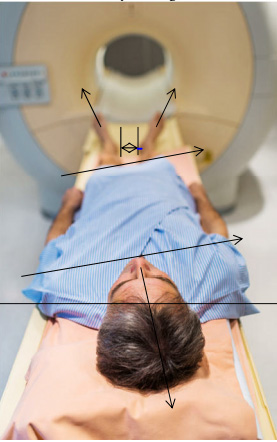

MRI- Röntgen-Bilder etc.

Abbildung: Ohne reproduzierbare Anhaltspunkte bezüglich Fussstellung und den Ausweichhaltungen wird eine Person in der entspannten Körperhaltung bebildert. |

Abbildung: Leider fehlen die erwähnten Angaben, |

Was kann eine solche Aufnahme ohne Muskelspannung aufzeigen? Über die Knieentlastung verändern sich Hüftgelenk- und Rückgrat-Stellungen. Wie kann somit eine Stellungsveränderung z.B. über eine einseitige Knieblockade, oder eine Stellungsveränderung der Beinschenkelwinkel zum Becken, eine schiefe Beckenebene festgestellt werden, die eventuell Gelenk oder Rückenbeschwerden verursachen können. Weiter verändert sich die Rückgrat-Stellung. Wie werden dabei Hohl- und Flachrücken im Zusammenhang beurteilt? |

Knie-Unterlage zur Entlastung Ein Körper ohne Belastung stellt wohl ein optisch genaues Bild dar, kann jedoch keine Auskunft über einen fehlbelasteten Körper geben. Dabei fehlen auch folgende Fragen: Haben Sie Angst, Angstinformation erhalten Alle diese |

- Bei den Bildgebenden Abbildungen weiss niemand wie diese zustande kamen und welchen Schmerzen die Person durch eine Entlastungshaltung ausgewichen ist.

- Ein Körper verändert sich über bequemes liegen durch entlasten der Bein/Knieachse und Kopfabstützung und dadurch verändert sich auch die Körper Spannung.

- Welche Körperhaltung wurde nun bei den Bildern dargestellt?

- Wieso fehlen die Mess-Aufnahme-Daten aus der statischen Körper-Mittellinie, damit ein Bild richtig interpretiert werden kann?

Wieso fehlen diese Statik-Angaben bei Bildgebenden Momentaufnahmen?

Körperaufnahmen in Schonhaltung werden Beschwerden sichtbar gemacht, ohne deren Ursachen zu berücksichtigen. Trotz optimaler Bildqualität und hochauflösender Aufnahmen werden die Ursachen der Beschwerden so nicht besser sichtbar, weil eine veränderte Muskelspannung auch eine veränderte Aufnahme zur Folge hat.